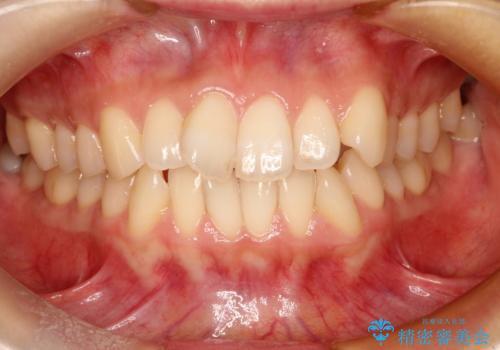

前歯のガタガタをインビザラインで目立たず矯正

- 目立たずに前歯を矯正したいとのことで来院されました。

歯と歯の間にわずかに隙間を作りスペースを確保し、インビザラインにて矯正を行うこととなりました。

前歯の微調整に少し時間がかかりましたが、整った歯並びにすることができました。